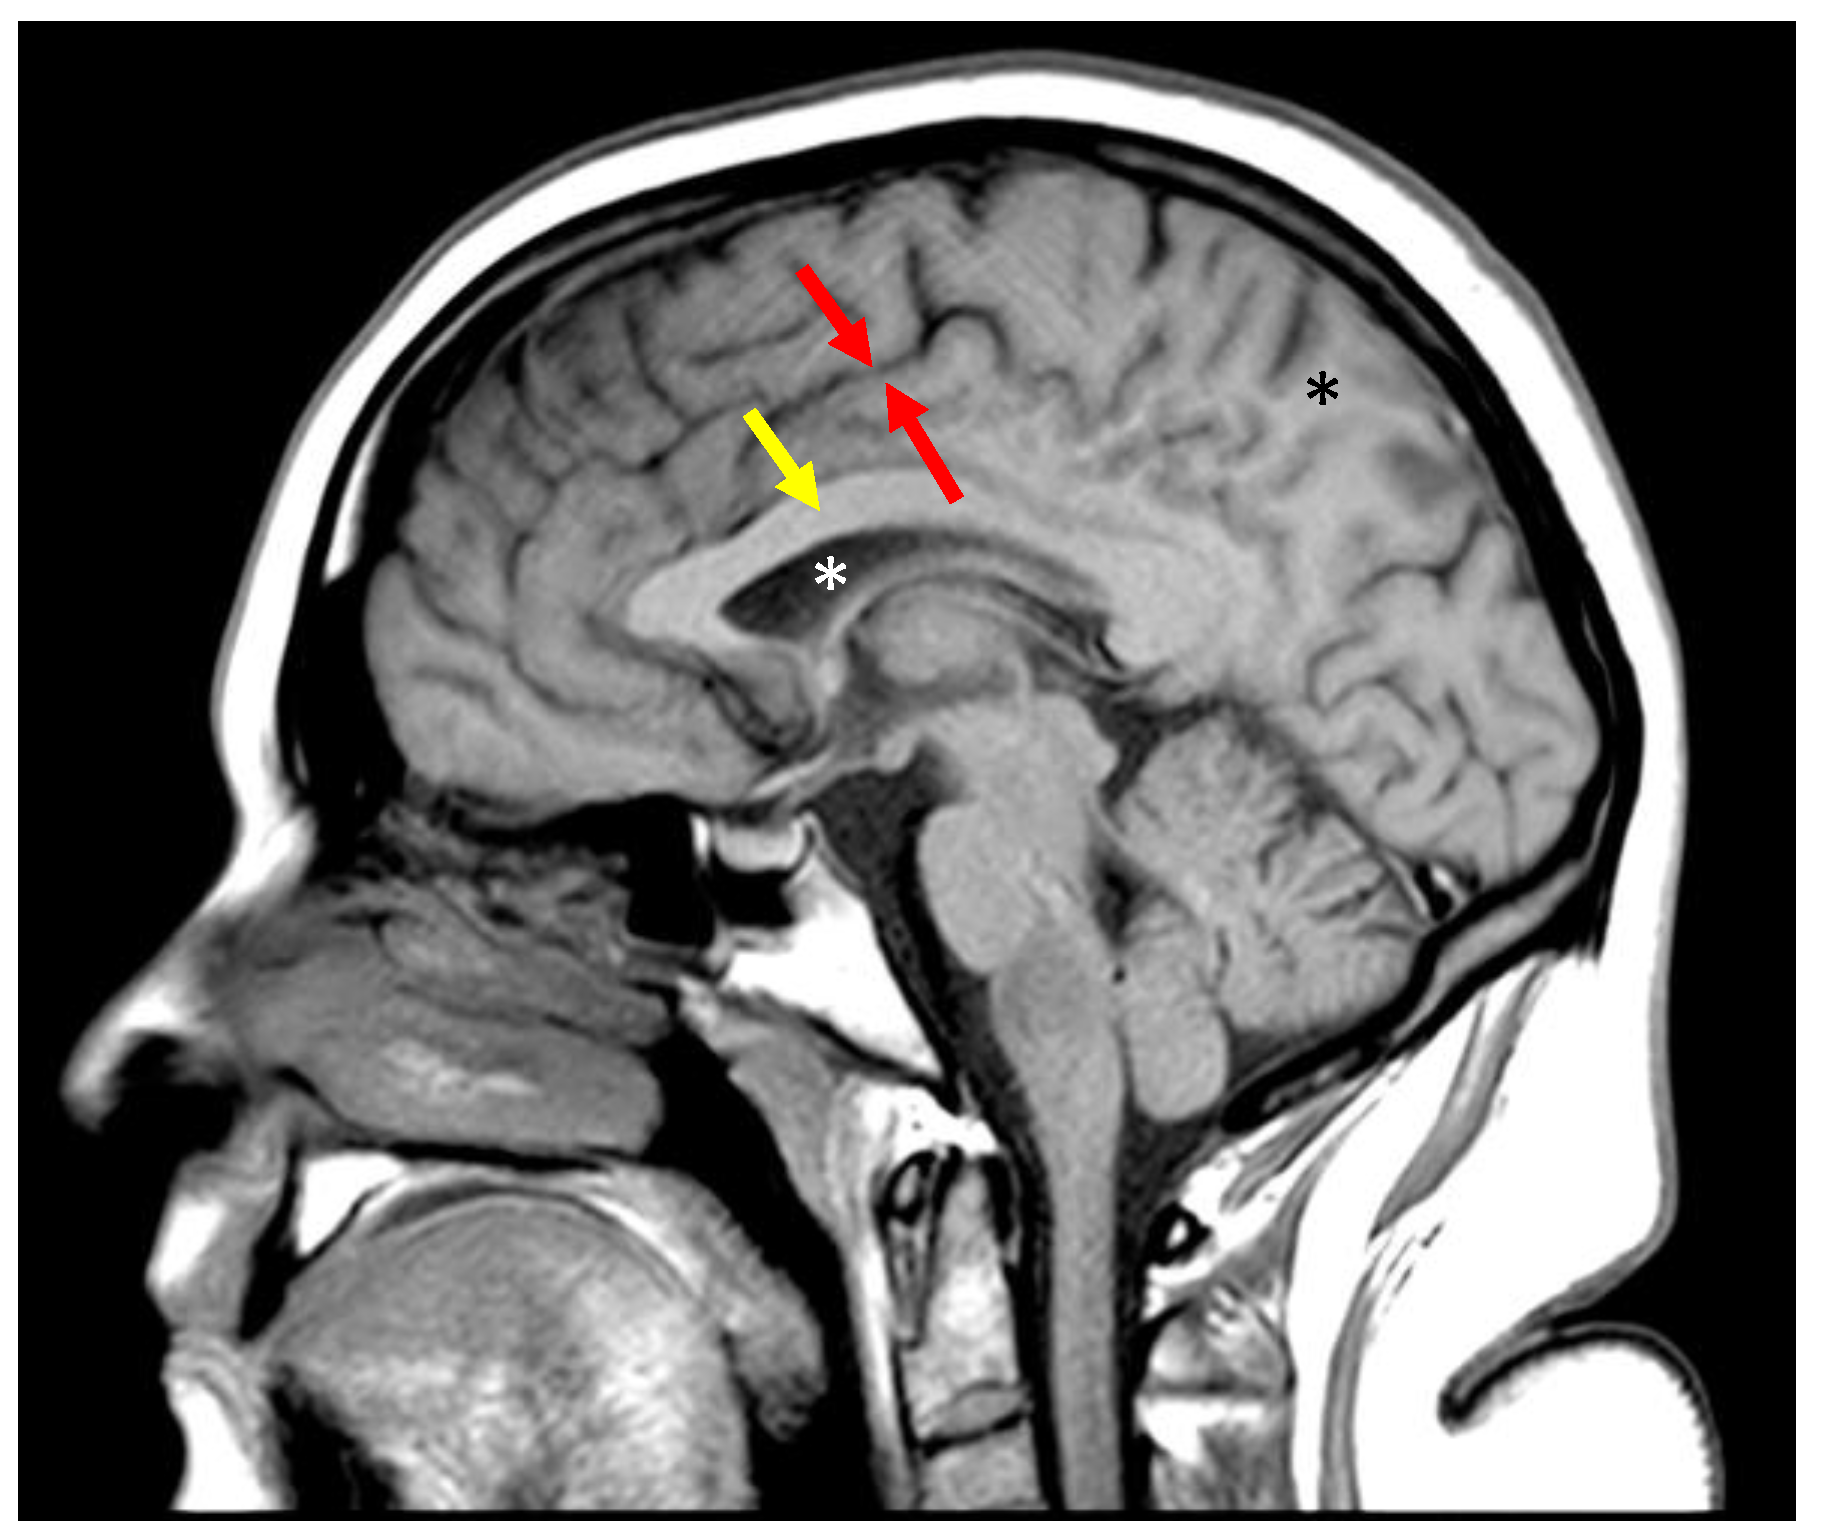

Figure 9.

Divided Subtracted Inversion Recovery (dSIR) images. (a) Sagittal dSIR image of the same slice and patient as in Figure 7a–c. TR = 5000 ms. TIshort = 450 to null white matter. TIlong = 850 to null gray matter. TE = 7 ms. This is considered a wide mD image. The normal white matter is black. A “Dawson’s finger” (red arrow) is seen as an increased signal. Small plaques (white arrows) are also identified as areas of increased signal. The increased signal is due to increased T1 in the abnormal white matter. The contrast on the image is described by the purple curve in Figure 8a. The contrast between the normal and abnormal white matter is 2.7 times that of the SIR image in Figure 5 and 5 times that of the IR image in Figure 7c. (b) Axial narrow mD dSIR in a healthy volunteer. TR = 5000. TIshort = 350. TIlong = 500. TE = 7 ms, TR = 5000 ms. The normal white matter is black. Normal gray matter is intermediate signal. There is a high signal boundary between the gray and white matter, because the tissue filter (purple graph in Figure 8b) has a maximum between the T1 values of white matter and gray matter. Note that the gray matter is not as bright as on the wide mD dSIR image, as in (a). Compare the y-axis values (signal) of the purple curves in Figure 8a,b at the T1 of gray matter.